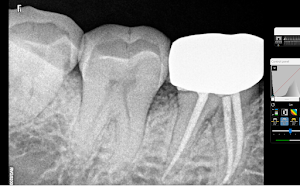

Welcome to our gallery

See how our company transforms ideas into reality. This gallery is a visual testament to our work and achievements.